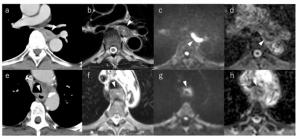

Does MRI Provide Better Staging of Esophageal Cancer than CT?